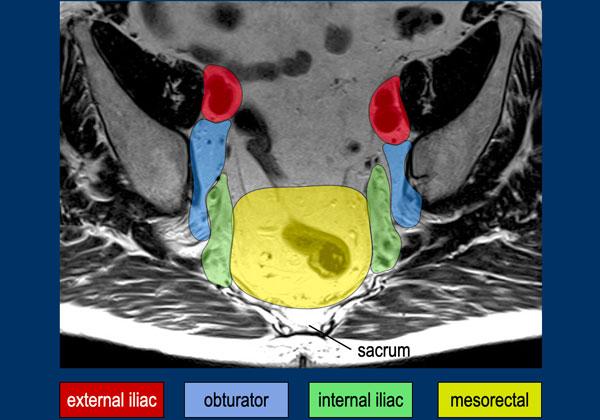

Phân loại N

Dẫn lưu hạch bạch huyết vùng. Các hạch bạch huyết màu đỏ đều là các hạch không thuộc vùng (giai đoạn M). Trong phẫu thuật TME, chỉ có các hạch mạc treo trực tràng và trong các khối u trực tràng cao còn có thêm các hạch trực tràng trên và hạch mạc treo tràng dưới được cắt bỏ.

Bản đồ hạch bạch huyết

Thuật ngữ về các vị trí hạch bạch huyết trong ung thư trực tràng có thể gây nhầm lẫn, với việc sử dụng không nhất quán các thuật ngữ như‘hạch ngoài mạc treo trực tràng’và‘hạch bên’để mô tả cả các trạm hạch bạch huyết vùng và không theo vùng.

Để lập kế hoạch điều trị chính xác, cần phân biệt giữa:

Hạch Bạch Huyết Vùng (phân loại cN)

- Các hạch mạc treo trực tràng (màu vàng): Bao gồm‘hạch bạch huyết trực tràng giữa cao’(lên đến nguyên ủy của động mạch mạc treo tràng dưới), nằm dọc theo các mạch máu mạc treo tràng dưới và trực tràng trên trước xương cùng.

- Hạch bịt (màu xanh lam)

- Các hạch chậu trong (màu xanh lá)

Hạch Bạch Huyết Không Thuộc Vùng (danh mục cM)

Các hạch bạch huyết nằm ngoài phân loại cN được coi là di căn xa (cM):

- Hạch chậu ngoài

- Hạch chậu chung

- Hạch bẹn

Lập kế hoạch Xạ trị/Phẫu thuật

Phẫu thuật TME tiêu chuẩn chỉ lấy bỏ các hạch mạc treo trực tràng.

Giới hạn trên của TME được xác định bởi vị trí khối u và hạch bạch huyết nghi ngờ ở vị trí gần nhất (tức là, liệu các hạch dọc theo động mạch mạc treo tràng dưới có được bao gồm hay không).

Báo cáo rõ ràng về sự tham gia.

Các hạch bịt và hạch chậu trong, dù thuộc phân loại cN, thường không được cắt bỏ thường quy—những hạch này có thể cần xạ trị mục tiêu hoặc phẫu thuật nạo vét hạch bạch huyết bên để giảm nguy cơ tái phát bên.

Ngoại lệ:AJCC TNM (ấn bản thứ 8) phân loại các hạch bẹn là hạch vùng đối với các khối u trực tràng thấp lan rộng vào ống hậu môn đoạn xa (dưới đường lược), vì các khối u này đi theo đường dẫn lưu bạch huyết vùng của ống hậu môn.

Hình ảnh MRI này minh họa

các khoang hạch bạch huyết trực tràng giữa, chậu trong, bịt, và chậu ngoài

như được phác thảo bởi Hiệp hội Nghiên cứu Hạch Bên[ref].

Những Điểm Chính:

- Các hạch chậu ngoài không phải là hạch vùng; nếu dương tính, chúng được phân loại là bệnh di căn (cM).

- Các khoang bịt và chậu trong được phân tách bởi bờ bên của thân chính của các mạch chậu trong.

- Ranh giới phía sau của khoang chậu ngoài được xác định bởi ranh giới phía sau của các mạch chậu ngoài.